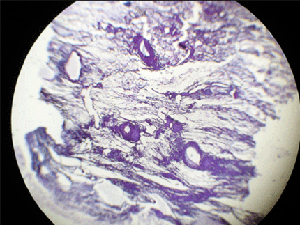

Во всех гистологических препаратах фолликулярного рака щитовидной железы при окраске толудиновым синим обнаруживался феномен метахромазии, стенки сосудов капсулы окрашивались в сиреневый и розовый цвета. Коллагеновые волокна стенок сосудов были подвергнуты фибриллярному разволокнению. В стенках большинства вен обнаружива-лось скопление фибрина темно-синего цвета (рис.1).

Рис 1. Скопление фибрина в стенках сосудов капсулы щитовидной железы. Окраска фибрина по Шуенинову. Фолликулярная карцинома щитовидной железы.